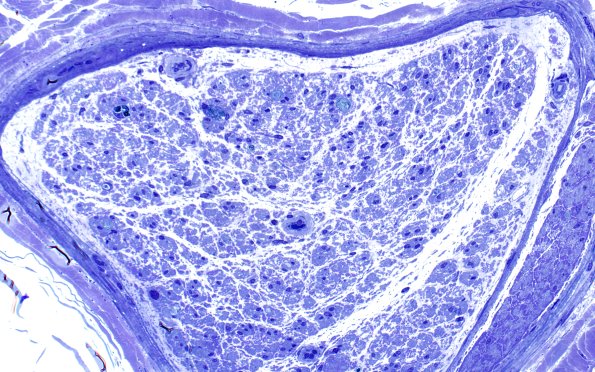

2D6 sarcoid & Chronic Denervation (Case 2) Plastic 40X 3

The loss of axons in most fascicles is nearly complete. (Plastic sections)